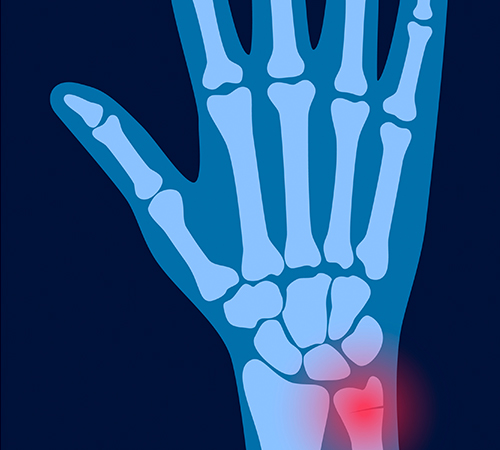

원위요골골절

• 정상

• 원위요골골절

골절 형태가 매우 다양하고 다른 부위의 손상도 동반될 수 있어

만성적인 불안정성을 유발하지 않도록 조기 치료가 중요합니다.

• 원위요골골절 진단

단순한 X-ray 검사로도 쉽게 진단됩니다.

관절이 심하게 침범된 경우, 컴퓨터 단층 촬영(CT)이 필요하기도 합니다.